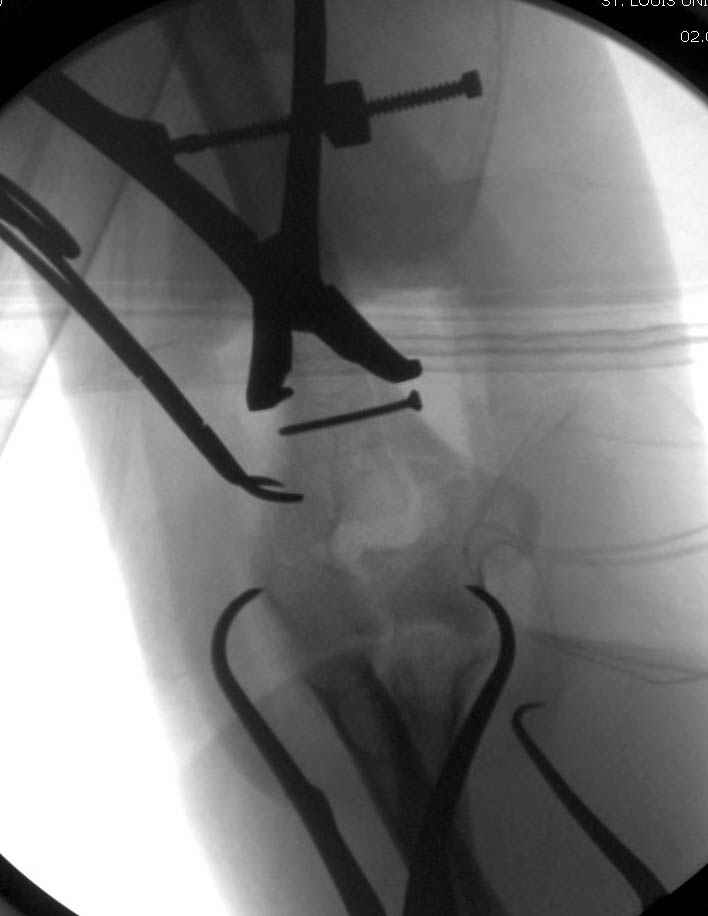

Примерный случай, только перелом был открытый, в задне-медиальной стороне рана около 2 см по характеру "изнутри кнаружи", неврологический статус со слабостью сгибания мизинца, также слабая абдукция и аддукция указательного пальца и сгибания в кисти.

Больному сделали обработку и наложили временный аппарат внешной фиксации плечо-предплечье.

На шестой день сделали открытую репозицию чрезлоктевым доступом двумя locking plate, локтевой нерв был ушибленным, после операции положительная динамика в Flexor Carpi Ulnaris. Фиксацию локтевого отростка произвели tension band technique с дополнительным шурупом.

Этапы операции на снимках....

Джолдас Кульджанов

Djoldas Kuldjanov, MD

Department of Orthopedic Surgery

St. Louis University Medical Center